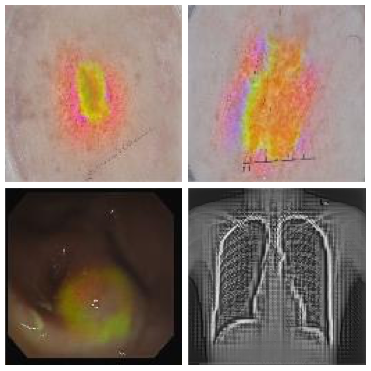

Improved Inference via Deep Input Transfer

Saeid Asgari Taghanaki, Kumar Abhishek, Ghassan Hamarneh

International Conference on Medical Image Computing and Computer Assisted Intervention (MICCAI), 2019

(Early Accept)

We propose an input image transformation technique that relies on the gradients of a trained segmentation network to transform the images for improved segmentation performance. [Abstract] [BibTeX]

Although numerous improvements have been made in the field of image segmentation using convolutional neural networks, the majority of these improvements rely on training with larger datasets, model architecture modifications, novel loss functions, and better optimizers. In this paper, we propose a new segmentation performance boosting paradigm that relies on optimally modifying the network's input instead of the network itself. In particular, we leverage the gradients of a trained segmentation network with respect to the input to transfer it to a space where the segmentation accuracy improves. We test the proposed method on three publicly available medical image segmentation datasets: the ISIC 2017 Skin Lesion Segmentation dataset, the Shenzhen Chest X-Ray dataset, and the CVC-ColonDB dataset, for which our method achieves improvements of 5.8%, 0.5%, and 4.8% in the average Dice scores, respectively.